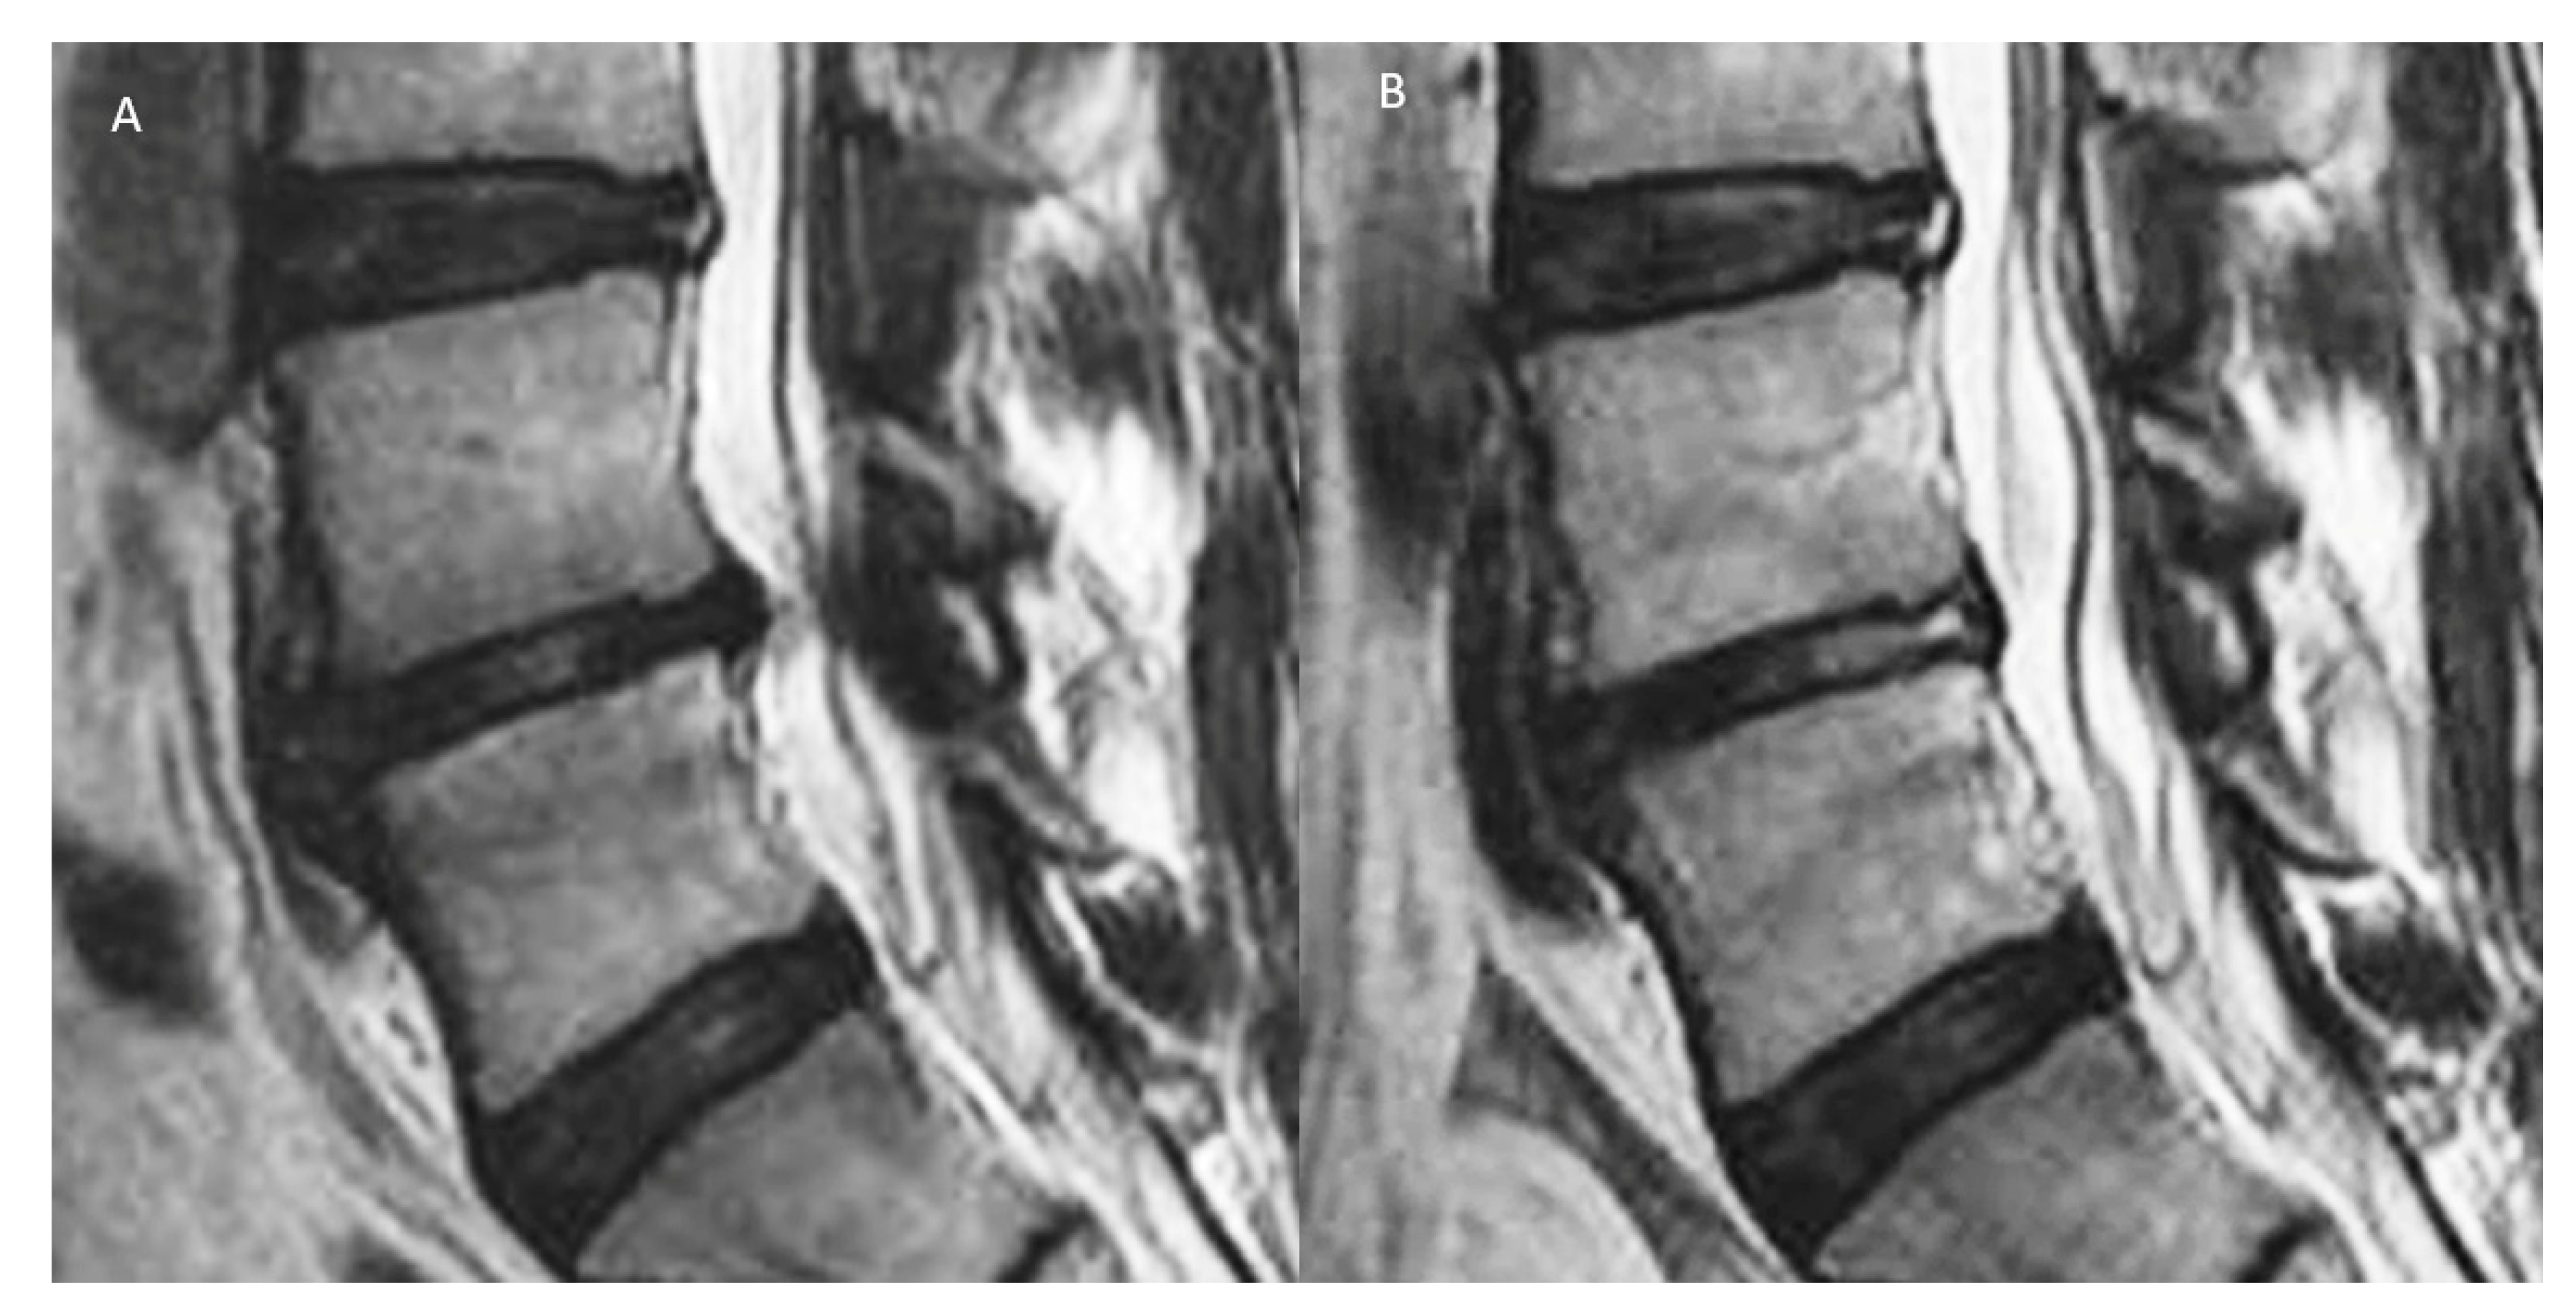

3.19. Modic Changes and Pain Simulation

3.20. Genetics and Its Effect on Pain Perception in Disc Diseases

- Kim, H.S.; Adsul, N.; Yudoyono, F.; Paudel, B.; Kim, K.J.; Choi, S.H.; Kim, J.H.; Chung, S.K.; Choi, J.-H.; Jang, J.-S.; et al. Transforaminal Epiduroscopic Basivertebral Nerve Laser Ablation for Chronic Low Back Pain Associated with Modic Changes: A Preliminary Open-Label Study. Pain Res. Manag 2018, 2018, 6857983. [Google Scholar] [CrossRef] [PubMed]